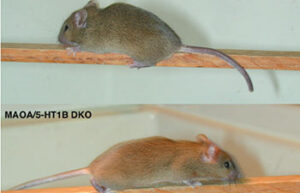

- Create and induce a variety of animal models